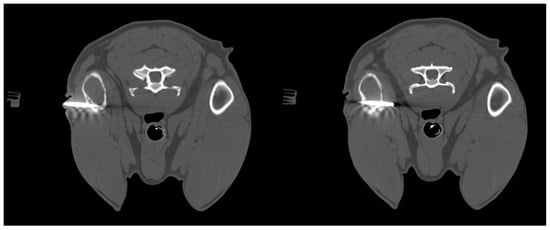

ROSE provides immediate feedback on sample adequacy, enabling a faster and more reliable diagnosis [10]. To increase the likelihood of obtaining diagnostic samples, multiple biopsies are usually performed on the same lesion. However, performing each biopsy, especially in dangerous anatomical locations, can cause complications. Therefore, the main objective of this study is to try to reduce the number of biopsies that need to be performed to obtain a diagnostic sample, thereby also lowering the risks for the animal. Analysis of the results of this study has shown that extemporaneous cytological examination can be useful for the purpose described above. In fact, out of 79 biopsies collected, extemporaneous cytological examination revealed cellularity in 81% of cases. The presence of representative cellularity in these samples made it possible to terminate the biopsy procedures. In the remaining cases, the lack of cellularity in the extemporaneous cytology suggested that further sampling should be carried out. Furthermore, it should be noted that in most of the samples in which no cellularity representative of the biopsied lesion was detected (25 out of 79), the cause was attributed to poorly stained and/or poorly fixed slides (technical problems), the presence of blood-contamination and poor cellularity due to the intrinsic nature of the sampled lesion. During the oncogenic process, blood may not arrive in sufficient quantities, causing an environment that is poor in oxygen (hypoxic) and nutrients (ischemic), which leads to necrosis, thus reducing the cellularity of the sample [13,14]. Furthermore, it is important to note that the interventional procedures in this study, excluding those performed with CT, were performed with 2D-mode ultrasound as shown in Figure 3. CT-guided biopsy sampling is, in fact, a procedure mainly indicated for bone lesions or lesions located in areas not easily accessible with US [6,15]. The relevance of this has been demonstrated in several studies reported in the literature as it can lead to several advantages. In the study by Vignoli et al. [16], in 2013, the importance of CT and guided biopsy in the staging of cancer patients was emphasized. In fact, although rare, muscular metastases can occur with different types of neoplasms. The most common sites of metastasis included the cervical, thoracic and lumbar paraspinal muscles, the chest wall, the scapular region, the hind limbs and, more rarely, the abdominal wall. The results highlight the importance of CT in the staging of cancer in dogs and cats, particularly in tumors with a high propensity for metastasis [14]. In this regard, for example, another study highlighted the frequency of muscle metastases in cases of hemangiosarcoma. Muscle metastases were found in 15/60 dogs (24.6%), all of which also had metastases in other organs. These data suggest that the use of whole-body CT and guided biopsy is essential in the staging of dogs with hemangiosarcoma, as muscle metastases may not be detected by clinical examination alone or by traditional imaging methods such as radiography and ultrasound [17]. Moreover, the intravenous injection of a non-ionic iodinated contrast medium provides additional vascular information about the lesion, allowing biopsy of viable tissue while avoiding major blood vessels and to sample the most representative portions of the lesion [8]. On the other hand, ultrasound is the method of choice in daily practice due to the wide availability of US equipment and its lower cost compared to CT [18]. In fact, as reported in some human literature, sampling of lung lesions visible with US is preferable [19]. Ultrasound can be used for real-time, multiplanar visualization, as well as for the accurate localization of target lesions that move with respiration. It also allows precise needle adjustment throughout all procedural steps. Additional advantages of ultrasound include the absence of radiation-related risks, its safety, speed, and cost-effectiveness [20]. Therefore, ultrasound has been recommended as an excellent option for guiding biopsies of peripheral pulmonary lesions [19]. Moreover, as demonstrated in some studies, the injection of contrast-enhanced ultrasound (CEUS) allows for the precise definition of the margins of the lesion, the identification of any necrotic areas, and the assessment of the distribution of vessels within it. The use of CEUS may be recommended to directly guide sampling procedures, improving the diagnostic success of cytological and histological examinations [21,22]. Therefore, paying particular attention to avoiding pre-analytical errors in the collection and/or preparation of slides, this method could prove particularly useful in interventional diagnostics.

Figure 3. Dog, Mixed breed, 8 y, spayed female. Percutaneous ultrasound-guided biopsy of liver mass. Final diagnosis: Well-differentiated carcinoma.